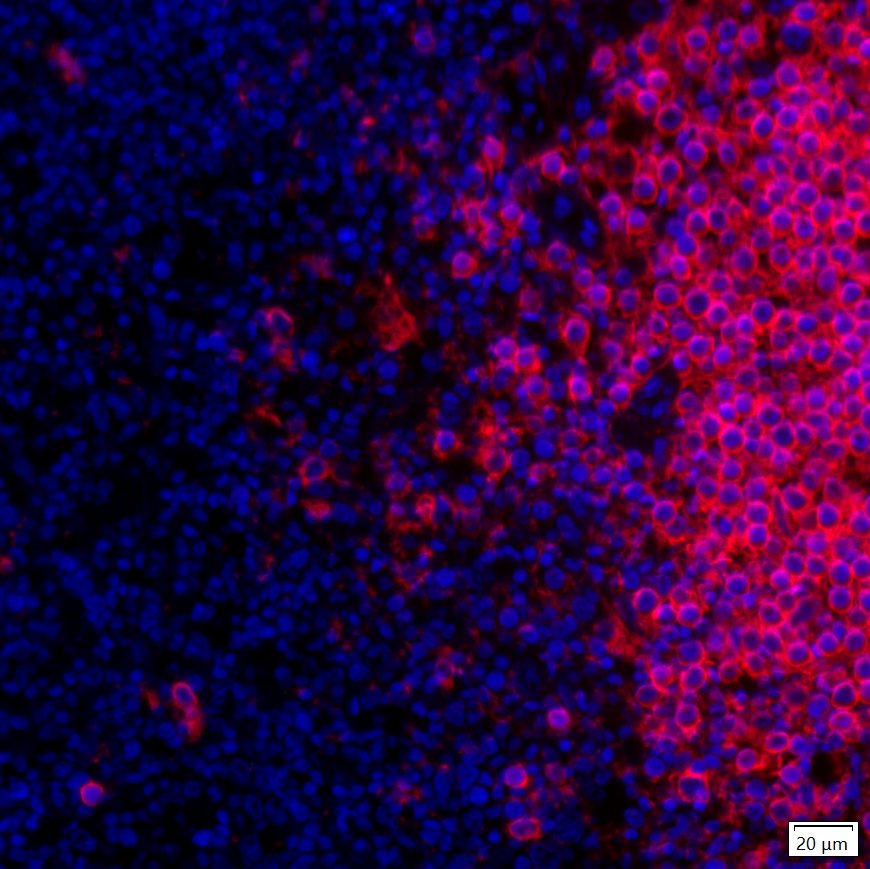

IRS003_9.jpg Fig9: mIHC analysis of human tonsil tissue (Formalin/PFA-fixed paraffin-embedded sections) with Rabbit anti-CD20 antibody (IRS003) at 1/100 dilution. The immunostaining was performed with the IRISKitCmTSA Kit (900808). Heat mediated antigen retrieval with Tris-EDTA buffer (pH 9.0) for 30 mins at 95℃. DAPI (blue) was used as a nuclear counter stain. Image acquisition was performed with Olympus VS200 Slide Scanner.

IRS003_10.jpg Fig10: mIHC analysis of human tonsil tissue (Formalin/PFA-fixed paraffin-embedded sections) with Rabbit anti-CD20 antibody (IRS003) at 1/100 dilution. The immunostaining was performed with the IRISKitCmTSA Kit (900808). Heat mediated antigen retrieval with Tris-EDTA buffer (pH 9.0) for 30 mins at 95℃. DAPI (blue) was used as a nuclear counter stain. Image acquisition was performed with Olympus VS200 Slide Scanner.